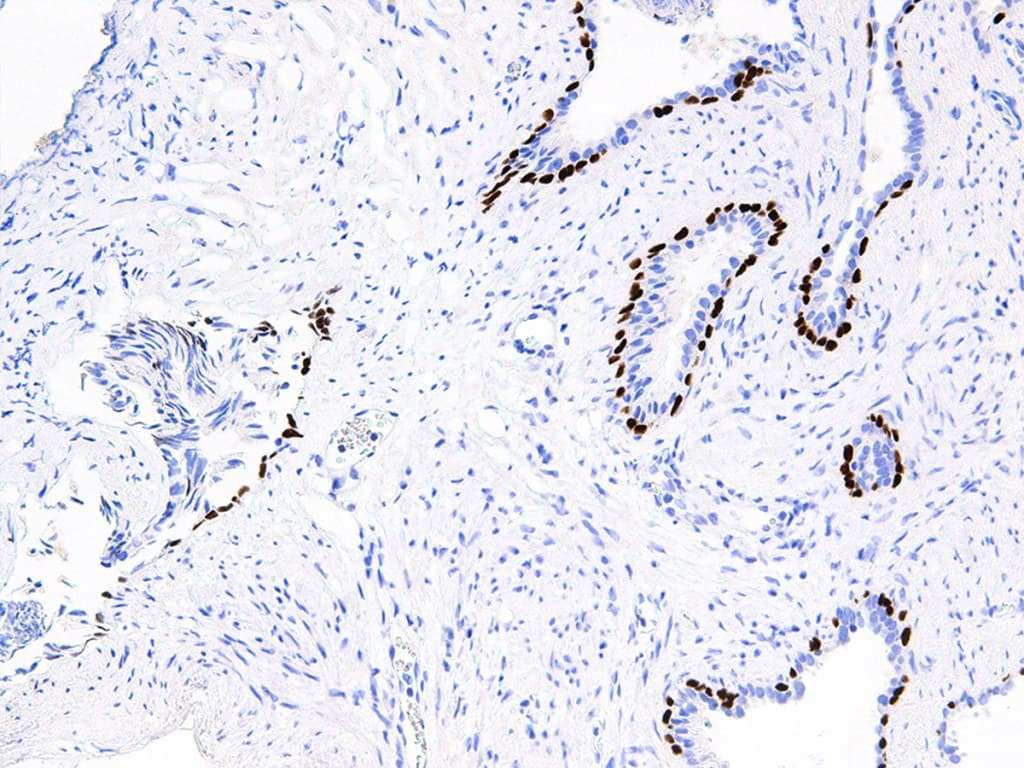

La p63 es una proteína supresora de tumores muy similar a la p53 en estructura y función, y homóloga a la p73. P63 se identifica en las células basales de las capas epiteliales de diversos tejidos, como la epidermis, el cuello uterino, el urotelio, la mama y la próstata. p63 es importante en el desarrollo y la diferenciación, y se ha identificado como un marcador útil para distinguir entre carcinomas de células escamosas de pulmón y adenocarcinomas. Se ha demostrado que p63 es un prometedor marcador específico de células basales complementario a la citoqueratina de alto peso molecular (HMW-CK), para el diagnóstico diferencial de lesiones prostáticas benignas y carcinoma prostático. El anti-p63 también se utiliza para diferenciar entre lesiones benignas y malignas de próstata y mama, debido a su marcaje de los núcleos de las células mioepiteliales en ambos tipos de tejido.

Sección de cáncer de próstata